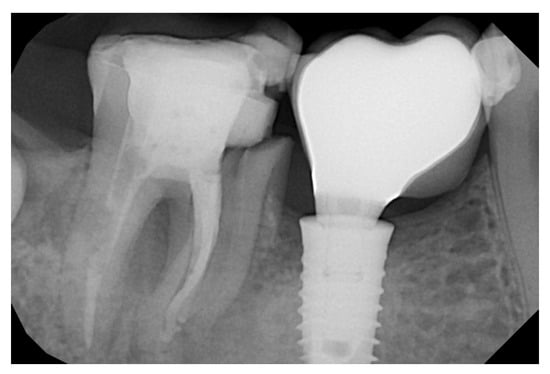

2.2. Surgical Technique

3. Results